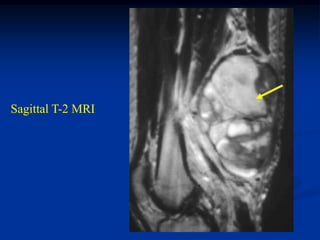

Case #1199

30 year male with

myxoid liposarcoma

posterior thigh

Sagittal T-1 MRI

Sagittal T-2 MRI

tumor

Axial T-1 MRI

Axial Gad contrast MRI

Coronal Gad

contrast MRI